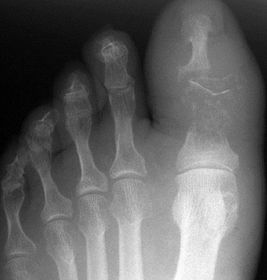

What disease is this? | Rheumatoid arthritis |